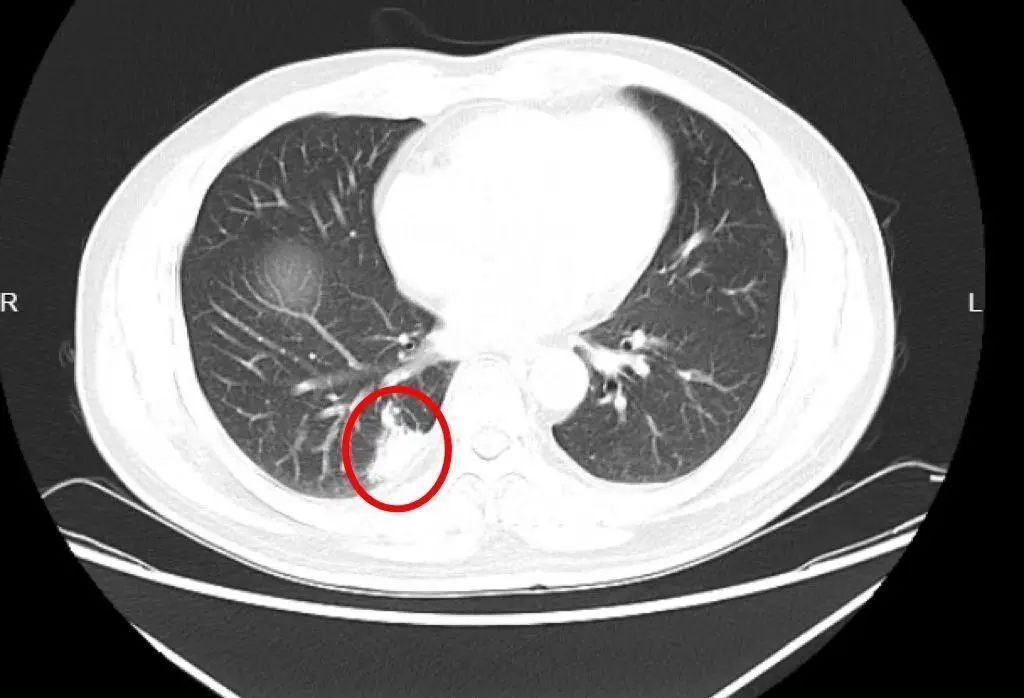

胸部CT:右下肺片结状影,考虑炎症和肿瘤性病变鉴别

陈绍森医生接诊后,根据胸部CT和临床经验,考虑黄叔肺部病灶经过消炎治疗后没有变化,可能不是简单的普通肺炎,并建议其住院进一步诊治。